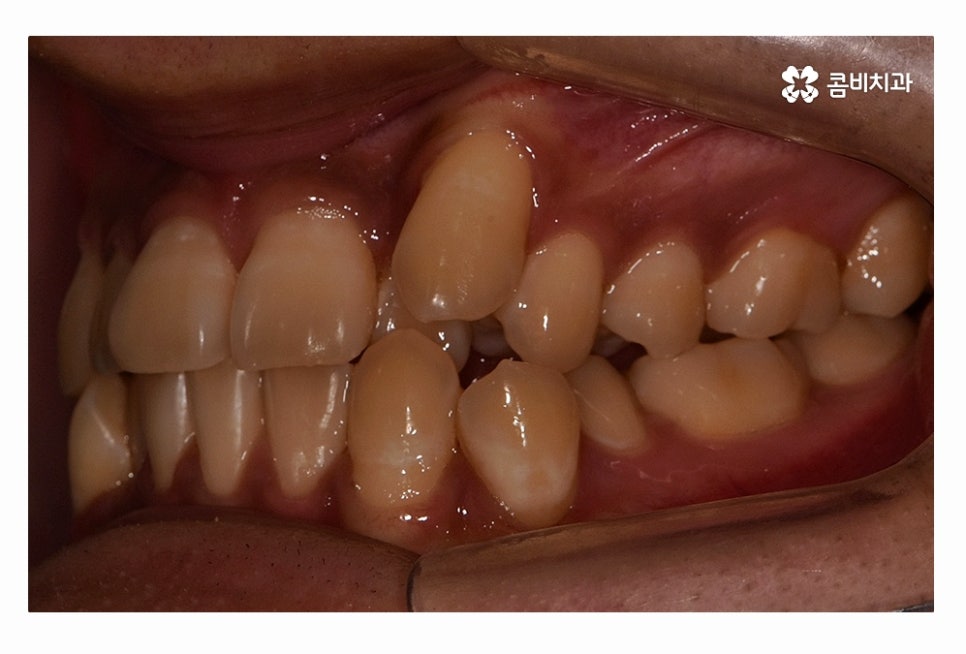

오늘 보시는 환자분의 사례처럼 덧니가 치아끼리 겹쳐 있는 경우에

치아의 이동 공간 확보를 위해서 덧니 발치 필요한 사례였으며

교합과 치아교정 후 얼굴 변화를 고려할 때도 치아교정 과정에서

발치가 필요한 사례였다고 볼 수 있어요.